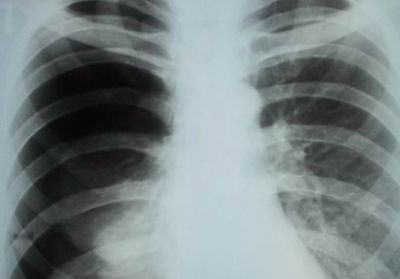

Пневмония

Если болит правый бок и отдает в спину как лечитьПредставляет собой воспаление легочной ткани, а именно альвеол, бронхов, соединительной ткани. Пневмония может быть двусторонней, левосторонней и правосторонней. Именно воспаление тканей правого легкого может провоцировать появление болей в правом боку и спине.

Характер и локализация боли

Правостороннее воспаление легкого характеризуется тупой болью в правом боку, локализованной преимущественно в подреберье.

При длительном течении заболевания боль ощущается в груди и спине со стороны пораженного органа.

При возникновении описанных выше симптомов необходимо обратиться к пульмонологу, который проведет осмотр и сбор анамнеза и назначит дополнительные диагностические процедуры, включающие:

• рентгенографию;

• КТ;

• фибробронхоскопию;

• клинические, биохимические и бактериологические исследования крови и отделяемой мокроты.